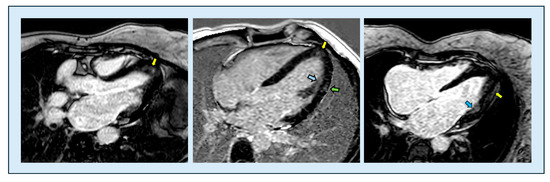

The use of non-invasive imaging techniques is undeniably one of the aspects that best characterize modern cardiology. With the implementation of percutaneous interventional procedures in the treatment of structural heart disease, and current advances in the management of chronic ischemic heart disease, metabolic storage diseases, and heart failure in clinical practice, imaging methods are required to provide increasingly sophisticated evaluation parameters, in order to adopt adequate therapeutic strategies and identify the patients best suited to undergo certain procedures. Therefore, clinicians in cardiac patient management cannot ignore the power of the complete and precise information provided by non-invasive diagnostic methods such as echocardiography, cardiac magnetic resonance imaging, cardiac CT, and nuclear cardiology, which can greatly facilitate correct diagnosis and adequate prognostic stratification.